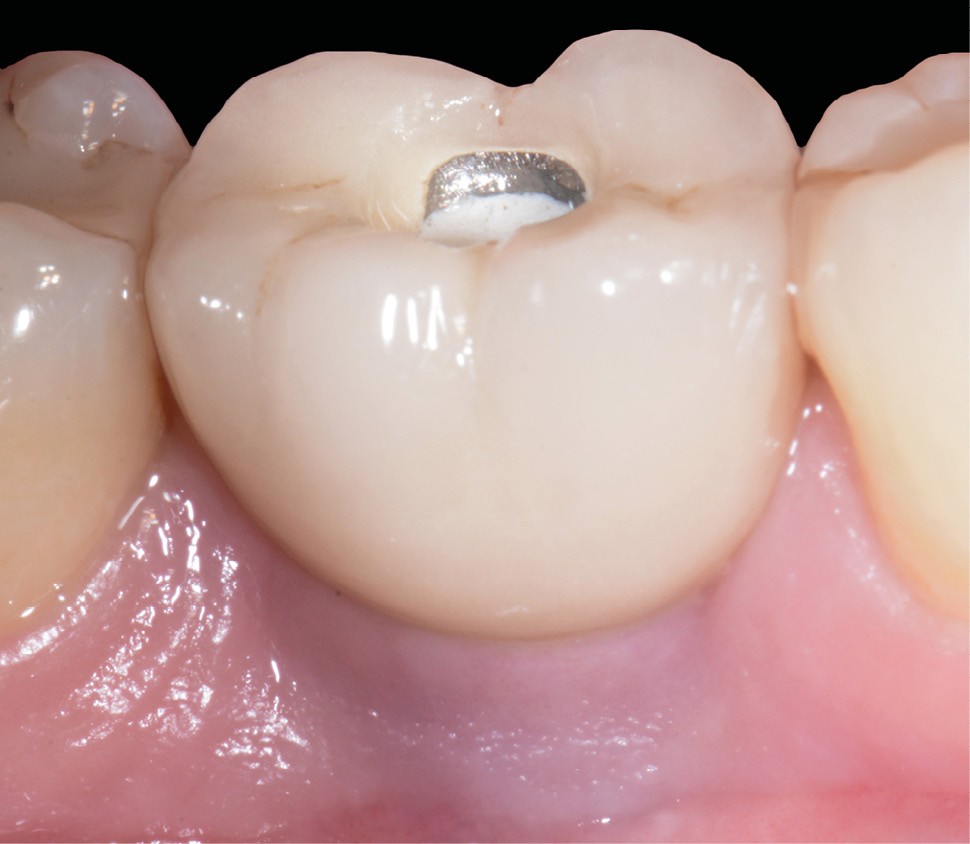

Les critères qui permettent de diagnostiquer une péri-implantite sont aujourd’hui bien établis, les voici rappelés : signes cliniques d’une inflammation péri-implantaire (gonflement, rougeur, saignement au sondage et/ou suppuration) (fig. 1a), perte osseuse péri-implantaire au-delà de celle constatée après la cicatrisation « initiale » (fig. 1b), augmentation de la profondeur de poche au sondage en comparaison de la profondeur de poche identifiée lors de la mise en place de la restauration prothétique [2, 23]. En l’absence de documents radiographiques préexistants, une perte osseuse supérieure ou égale à 3 mm en association avec un saignement au sondage et une profondeur de poche au sondage supérieure ou égale à 6 mm permet également de poser le diagnostic de péri-implantite [23].